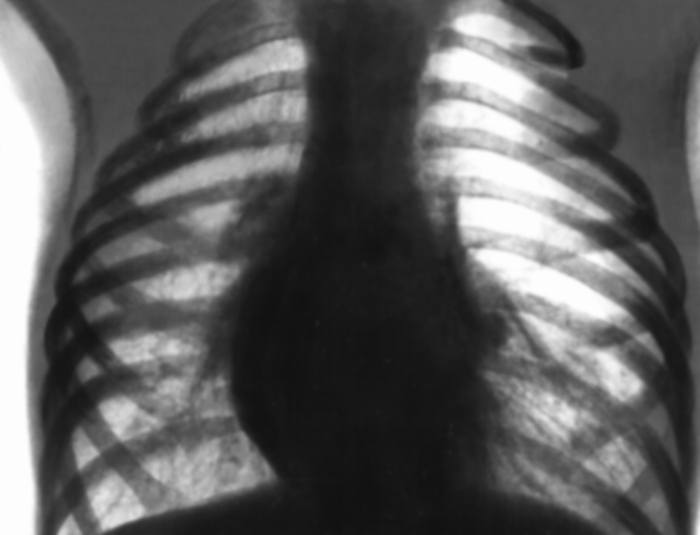

Эмфизема легких на рентгенограмме